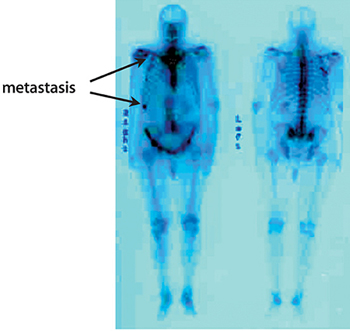

El estudio de los huesos mediante gammagrafía ósea debe ser efectuado si hay sospecha de lesiones óseas y/o el PSA es superior a 10 ng/ml. En ocasiones se realiza un PET-TC con colina para evaluar la presencia de metástasis.

Gammagrafía ósea. Es una prueba que nos permite detectar si el tumor ha invadido los huesos. Se realiza inyectando un isótopo radiactivo en la vena que se fija en las zonas donde el hueso esta dañado. Una cámara especial detecta los acúmulos de radiactividad y forma una imagen de todo el esqueleto. Estos acúmulos también aparecen en casos de lesiones inflamatorias (artritis), antiguos traumatismos u otras patologías óseas.